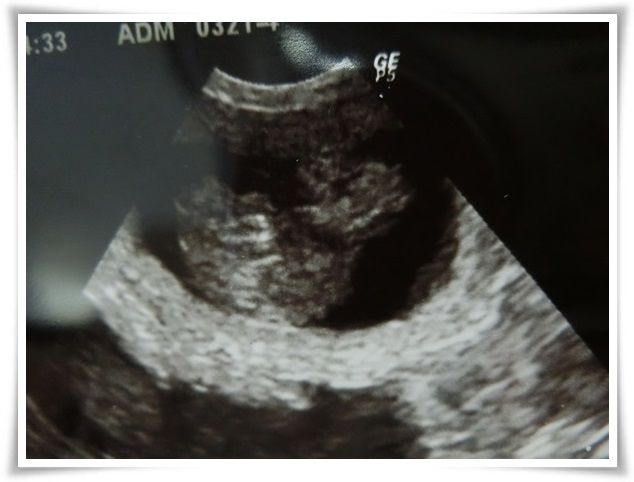

メリアは偏食することなく、モリモリ食べるようになりました。

体重が1日で200gも増えてます(汗)

お腹周りも1㎝増。